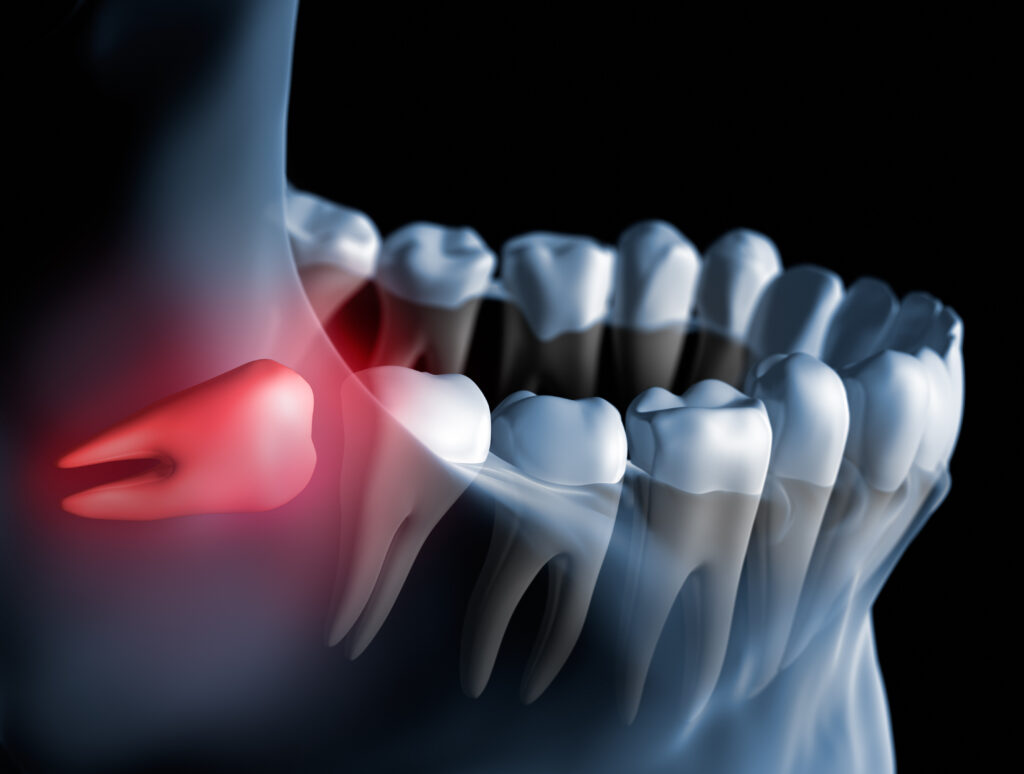

奥歯の後方に歯が生える余裕がない場合、親知らずは正常な位置に出てこられず、歯ぐきや骨の中にとどまってしまうことがあります。

このように、外から見えない状態で存在している歯を「埋伏歯(まいふくし)」と呼びます。完全に骨の中に埋まっている場合、見た目だけでは判断することは難しいです。

歯ぐきが腫れる、奥歯が痛む、口が開きづらいといった症状がある場合は、埋まってる親知らずが炎症を起こしている可能性があります。放置するとむし歯や歯周病の原因になることもあるため、早めの受診をおすすめします。

横向きに埋まっている親知らずが、手前の歯を押すことで歯並びに影響を与えることがあります。とくに矯正治療後の後戻りを心配される方は、一度確認すると安心です。